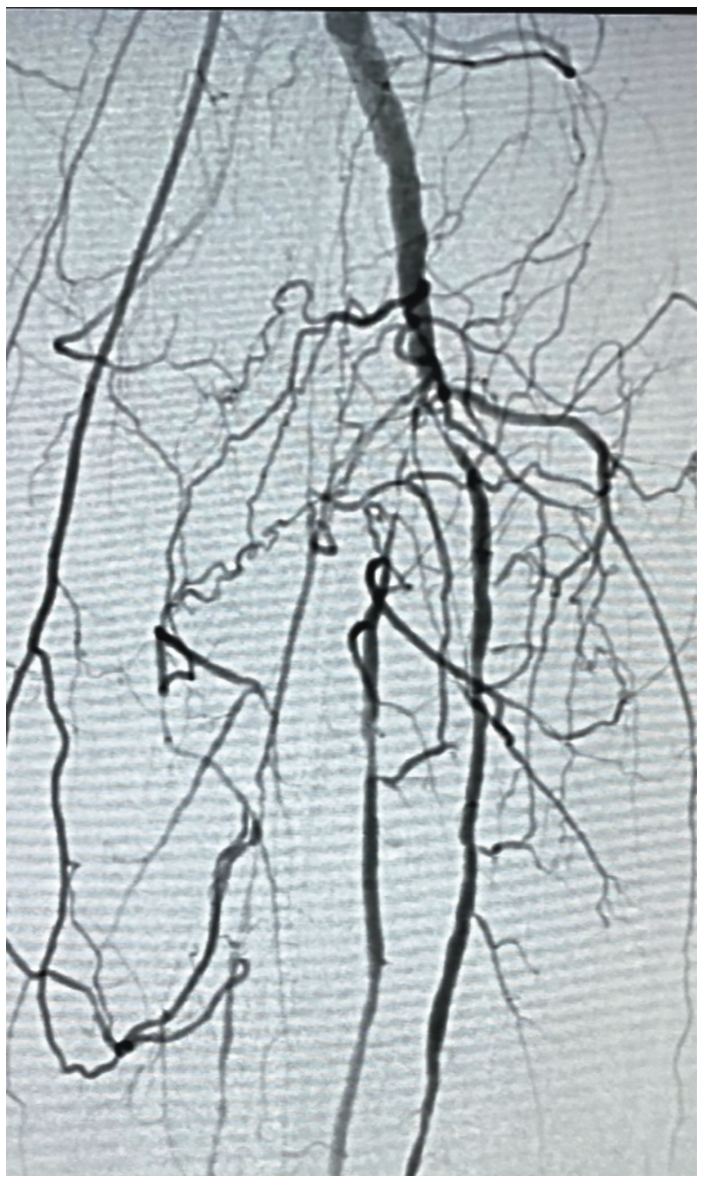

The most significant stenoses were in the popliteal artery and below the knee (BTK) (Figure 1):

• Popliteal: 90% stenosis

• Anterior tibial (AT): 99% subtotal occlusion

• Proximal tibial peroneal trunk (TPT): 80% stenosis

• Posterior tibial (PT) artery: 100% occlusion